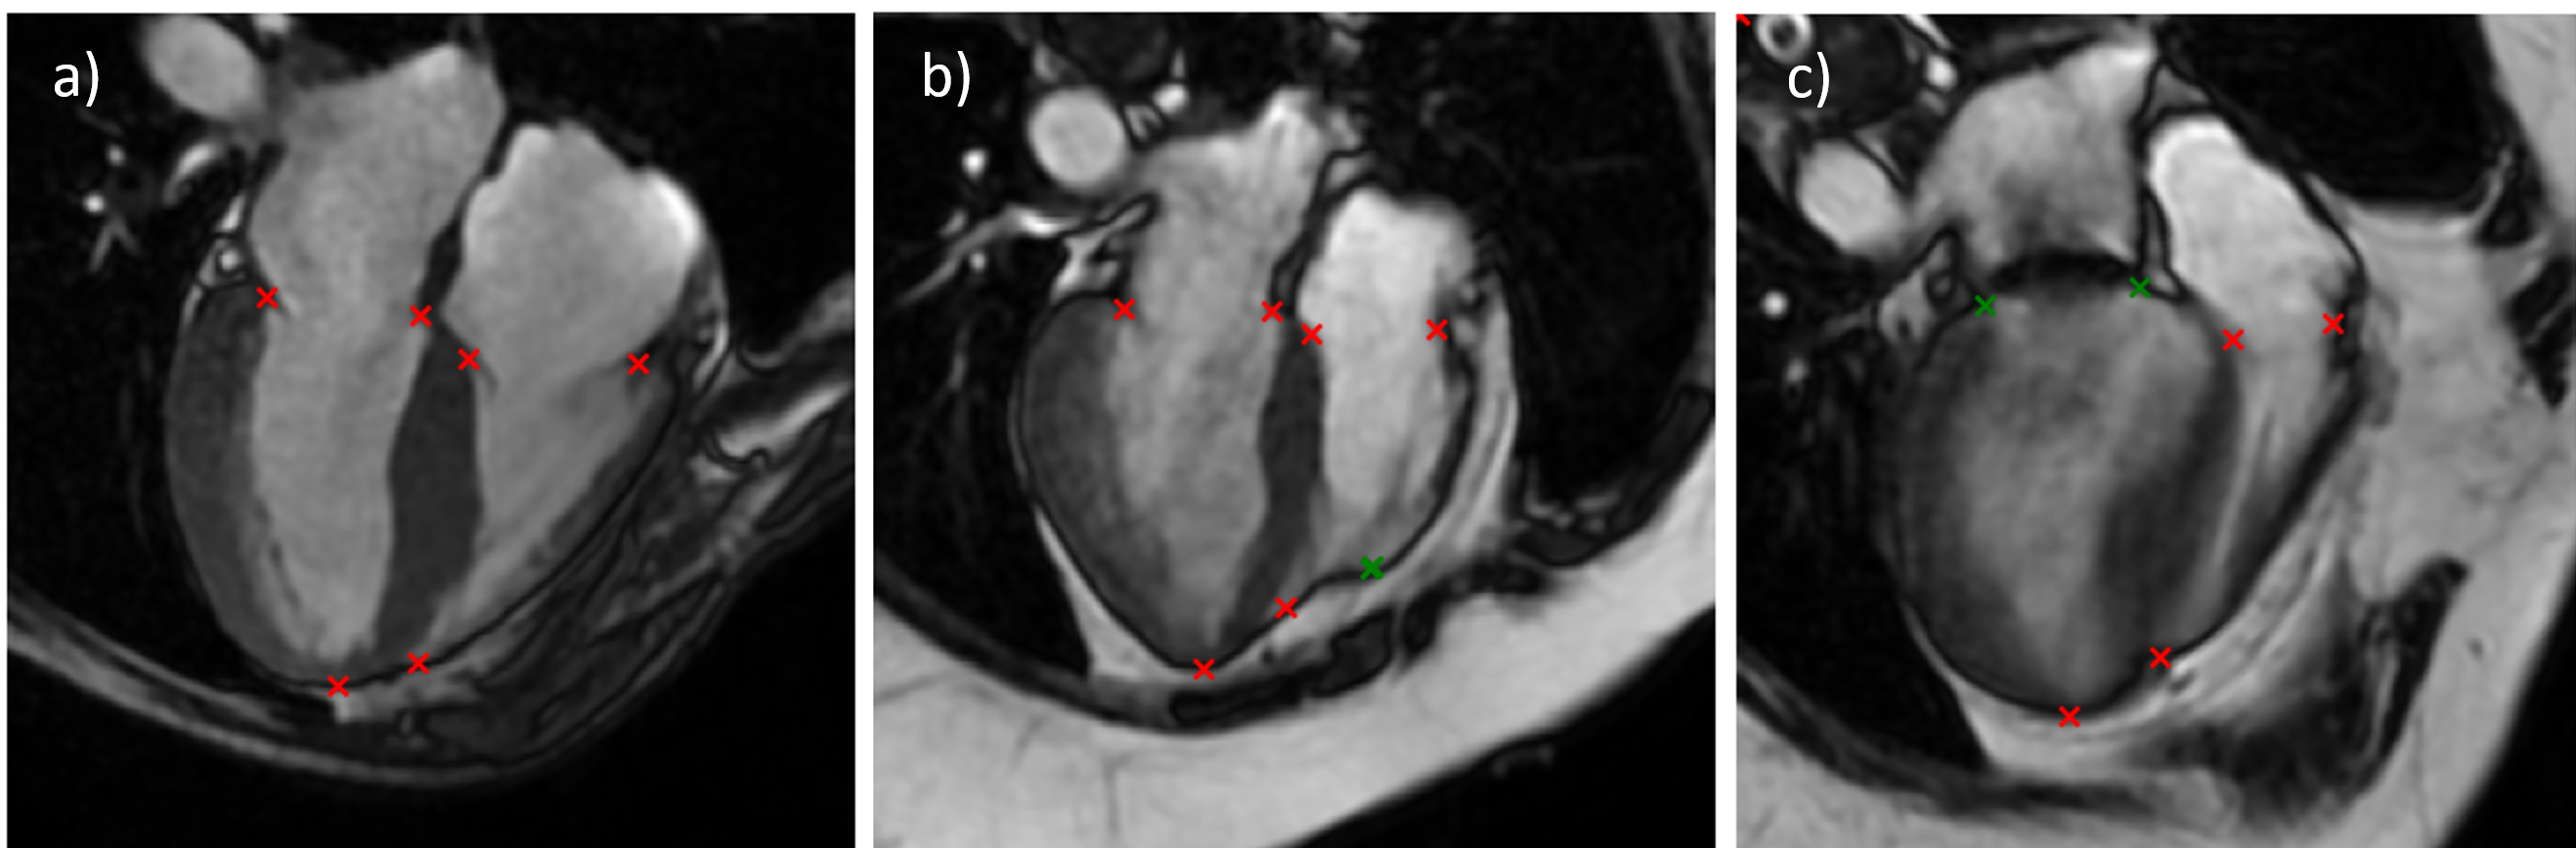

Landmark | Not detected | Misplaced |

Mitral valve (left) | 7 (4.3%) | 0 (0.0%) |

Mitral valve (right) | 2 (1.2%) | 0 (0.0%) |

Tricuspid valve (left) | 3 (1.8%) | 1 (0.6%) |

Tricuspid valve (right) | 5 (3.1%) | 0 (0.0%) |

Apex (left) | 0 (0.0%) | 2 (1.2%) |

Apex (right) | 5 (3.1%) | 14 (8.6%) |

Figure 2: Histograms showing the reviewer’s corrections for each landmark misidentified by the model.